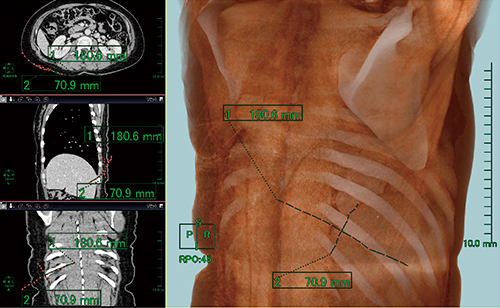

さらに,広背筋を術中に取り出すための切開位置の設定では,3D計測ツールの直線計測を使用し,3D画像上に,できるだけ体表面に沿うように肋骨と平行に直線を引き,執刀医の指示にて長軸18cm,短軸7cmとした(図5)。そして,この直線が対角線となるひし形の領域を切開範囲として設定し,その領域に含まれる脂肪組織を抽出し(図6 a,b),体積を測定した(図6 c)。この値を脂肪組織体積((3))とした。また,このレイヤーも保存した。

図5 広背筋摘出のための切開位置の設定